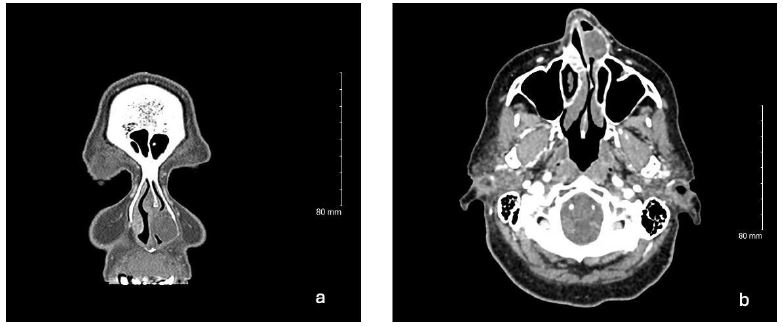

Histopathological analysis demonstrated the presence of a submucosal lesion comprised of ductal epithelial cells, rare squamous nodules, ovoid to spindled myoepithelial cells and chondromyxoid stroma. Gross examination revealed a mass measuring 2.5×1.9×1.2 cm with bone and cartilage. Immunohistochemical staining was positive for pan-cytokeratin and Cam 5.2 in tubules as well as S100 in myoepithelial cells. The sample was negative for NSE (Neuron Specific Enolase), Synaptophysin and INSM-1. The histomorphological features are compatible with a pleomorphic adenoma without evidence of malignancy (Figures 2-4).

Figure 2: H&E section at 200X magnification demonstrates a benign pleomorphic adenoma. Ovoid to spindled myoepithelial cells and chondromyxoid stroma present.